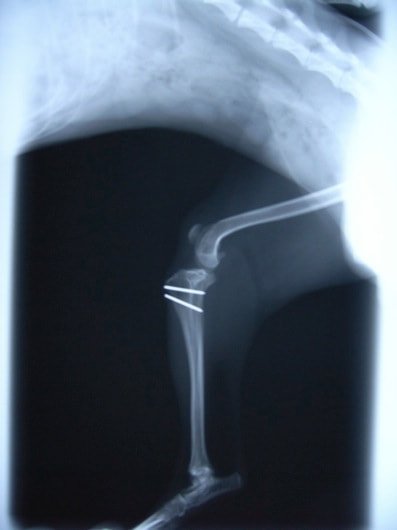

■ 症例22 ポメラニアン 1歳5か月 去勢雄

左後肢の挙上を主訴に来院した。整形学的検査、レントゲン検査より左右の膝蓋骨脱臼(左GradeⅡ〜Ⅲ、右Grade Ⅱ)を認めた。また、脛骨の前方引き出し試験の際に、引き出し兆候は認められないものの、疼痛が認められたため、前十字靭帯の損傷が疑われた。術中における、目視および関節内の操作によって、前十字靭帯の損傷や過伸展といった異常が認められなかったため、膝蓋骨脱臼の整復のみ実施した。手術手技は縫工筋及び内側広筋の解放、脛骨粗面の外側転位、滑車ブロック形造溝術、内外側関節包の縫縮を実施した。本症例は跛行もなく経過良好である。しかし、頸骨高平部の角度(TPA)が 右26.2°、左24.9°であり、解剖学的に前十字靭帯損傷のリスクが高いことから今後の経過に注意が必要である。